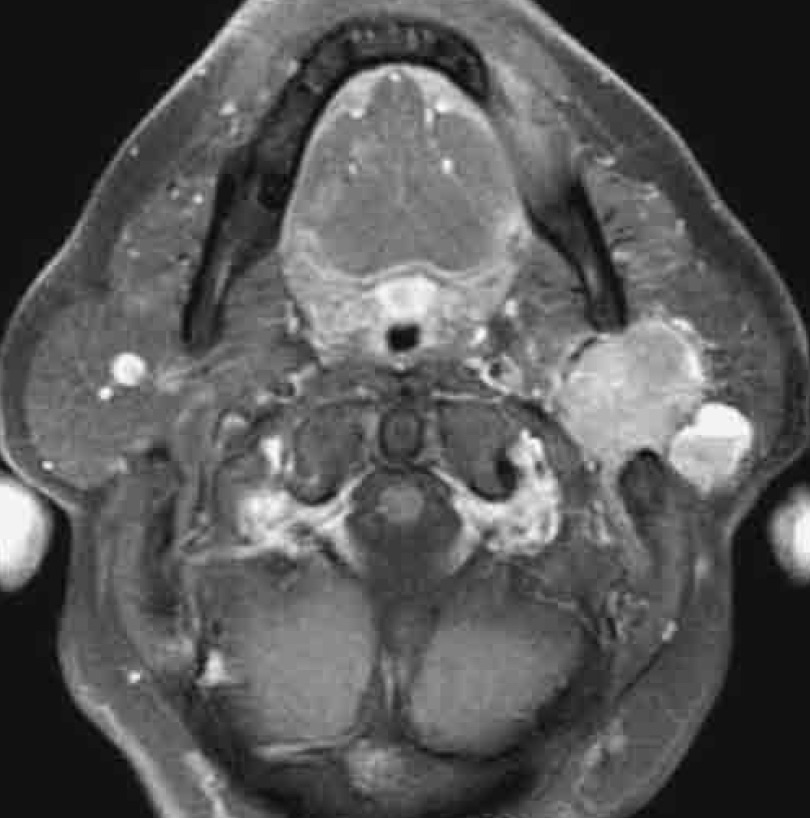

A part dans le cas des lymphomes et des tumeurs métastatiques, le traitement idéal des tumeurs parotidiennes bénignes ou malignes est chirurgical. Dans les rares cas où l’état de santé du patient est une contre-indication à la chirurgie, on préconisera un traitement conservateur basé sur le suivi clinique et radiologique. Lors de votre consultation, une anamnèse détaillée ainsi qu’un examen clinique minutieux permettront au Dr Yousefpour de cerner au mieux votre condition. Il complétera sa mise au point en demandant des examens complémentaires tels qu’une IRM (imagerie par résonance magnétique également appelée RMN ou résonance magnétique nucléaire) ainsi qu’une biopsie écho-guidée (examen lors duquel le radiologue performera une biopsie guidée par échographie). Au terme de cette mise au point le Dr Yousefpour discutera avec vous le diagnostic, le pronostic ainsi que les différentes options de traitement.